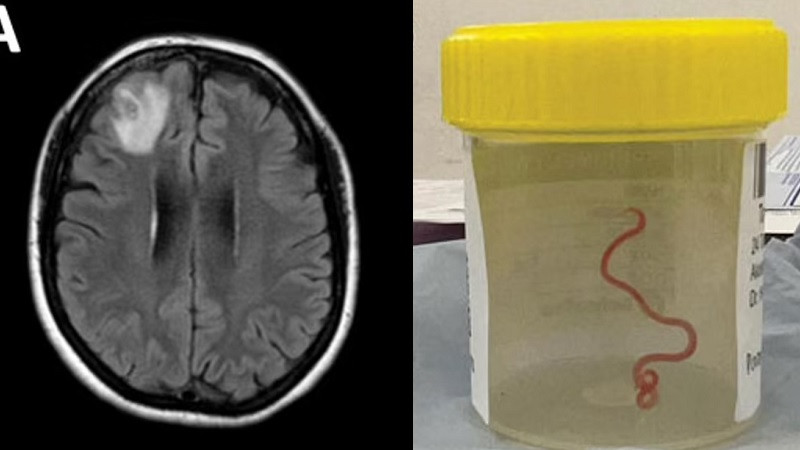

В январе 2022-го женщина начала страдать от забывчивости и депрессии, что заставило врачей обратить внимание на её мозг. МРТ показала повреждения в мозгу, после чего врачи решили провести операцию, во время которой они и обнаружили в мозге странную «струну», которая начала извиваться прямо на их глазах.

Червя удалили, а во время последующих операций никаких других следов паразита в теле женщины обнаружено не было. Спустя полгода после удаления червя состояние женщины улучшилось: забывчивость и депрессия не такие сильные, но всё равно ещё присутствуют. Врачи теперь проводят регулярное обследование пациентки, так как известно, что яйца такого червя могут сохраняться в организме более четырёх лет.